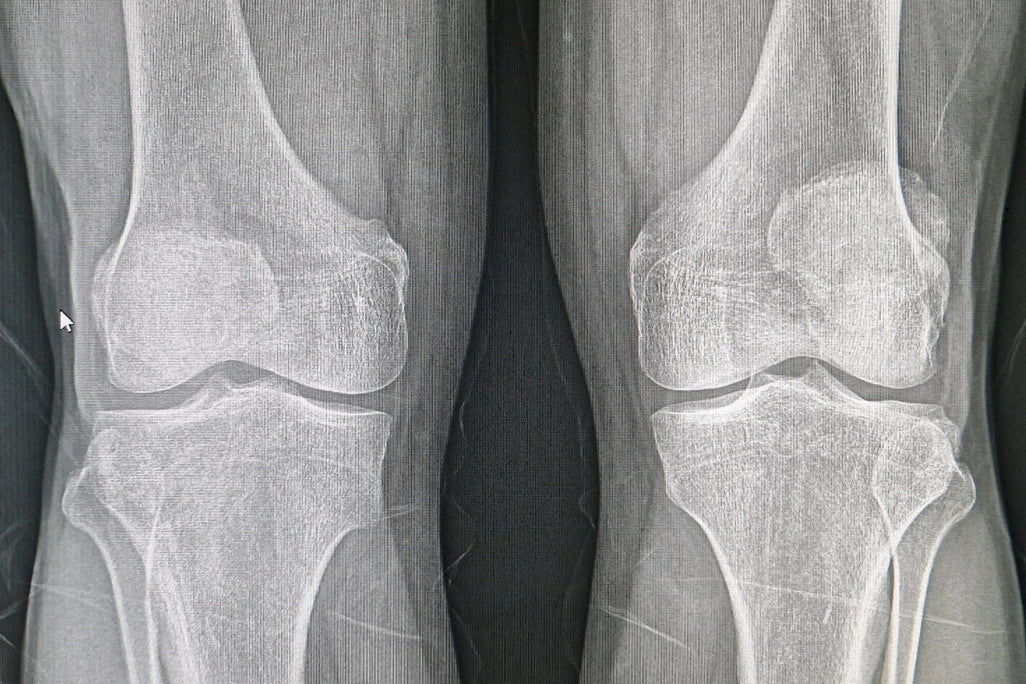

Mr. Maejima's bone density had risen from 2.71mmAI to an impressive 3.00mmAI—a dramatic increase of 10.7%.

Mr. Maejima applied the cream consistently as part of his treatment protocol. What followed was more than a slow recovery—it was a transformation. Not only did his bone density improve significantly, but his comfort, mobility, and outlook on life did as well.

For people like Mr. Maejima, and potentially millions more, the difference isn’t just on a chart—it’s in their everyday life. Being able to move without pain, walk confidently, and regain independence are priceless victories.